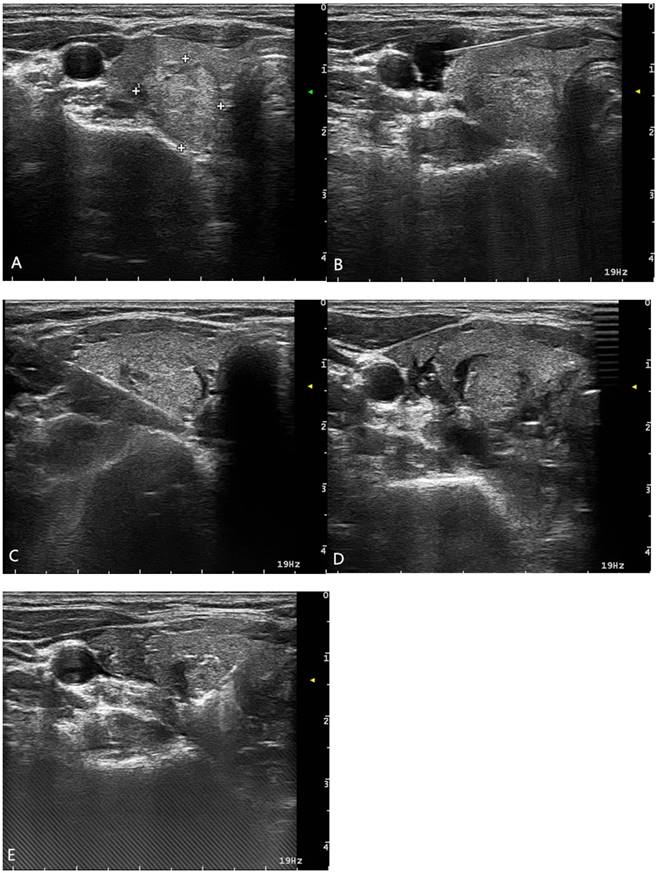

For each patient in the period of 2016.8- 2017.5, risk assessment was performed for all nodules and “hydrodissection technique” was used for nodules of Grade 1-3 before the ablation to ensure the safety. An example of a patient with a nodule of Grade 3 was shown in Figure 3.

Figure 3

A patient with a nodule of Grade 3. (A) Preoperative US, (B) Sterile water was injected along the carotid sheath, (C) Sterile water was injected into the backside of the thyroid, (D) Sterile water was injected into the space between the trachea and the thyroid gland, (E) Ablation with the Hydrodissection technique

J Cancer Image